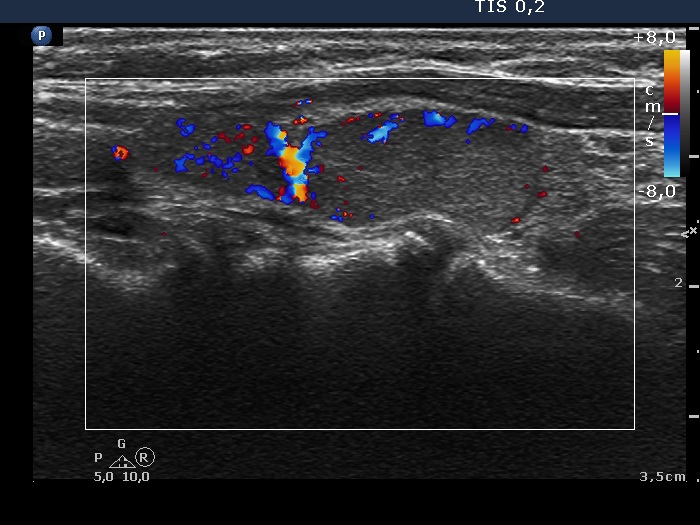

Follow-up examination 3 years later (second row of images):

Ultrasonography: The thyroid was unchanged. The lesions in the dorsal part of the right lobe increased in size and a small hypoechogenic area appeared in the ventral part of the left lobe.

Scintigraphy disclosed parathyroid enlargement not only in the right but even in the left side.